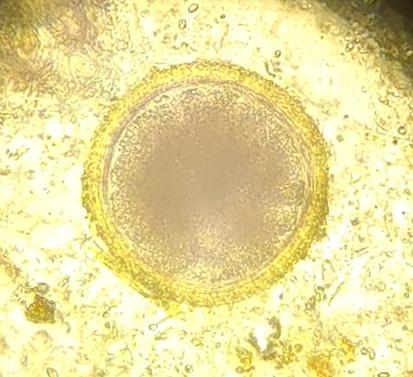

Prevalencia de parasitosis entéricas transmisibles de perros domésticos a humanos en la ciudad de La Paz, Bolivia

Prevalence of enteric parasitosis transmissible from domestic dogs to humans in La Paz city, Bolivia

Camila Isabel Palma Tovar, Marisol Colquehuanca Vino, Helen Condori Canaviri, Gina Gabriela López Blanco, Grisel Mireya Mamani Tuco, Carla Irene Paricollo Ancasi, Damaris Lindsay Quisbert Bautista, Valery Nayely Silva Molina..............................................................43-50